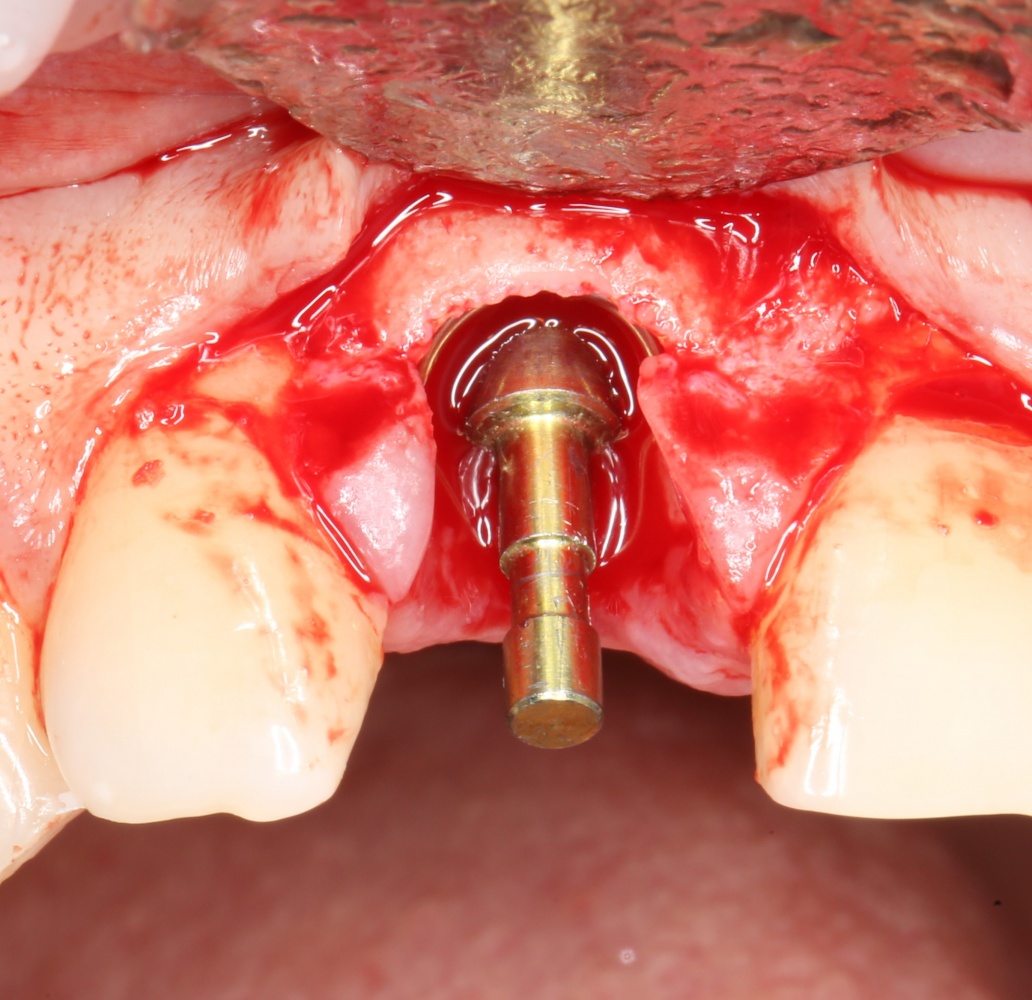

Все началось с воспаления, свищевого хода и удаления зуба:

Затем, мы готовим лунку и проверяем позиционирование импланта:

После чего аугментируем лунку. Для упаковки Bio-Oss Collagen очень удобно использовать аналоги имплантов:

Устанавливаем имплантат XiVE (Dentsply Implants):

Сразу на имплантат — временная коронка: